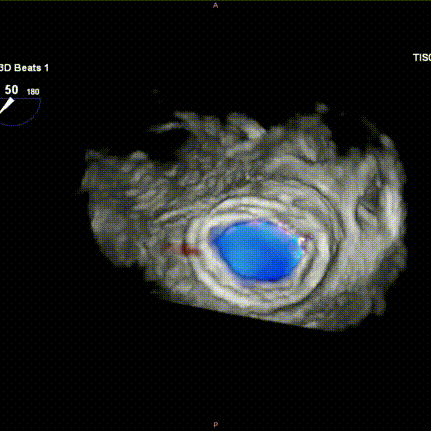

Figure H-I: Post-release TEE examination indicated stable valve position, good function, and no paravalvular leak.

7. Intraoperative left ventricular angiography immediately showed that the Mi-thos biological valve was well positioned and shaped, with no intravalvular regurgitation, paravalvular leak (PVL), or left ventricular outflow tract obstruction (LVOTO) observed (the new left ventricular outflow tract area was 374.6 cm²); TEE further assessed the valve position and function, showing an average transvalvular pressure gradient of 3 mmHg.